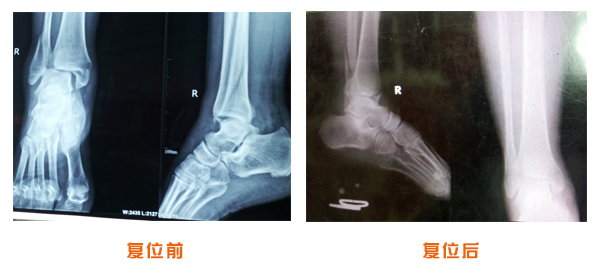

肥城市安駕莊梁氏骨科醫(yī)院是一所以梁氏手法正骨配合膏藥為特色的現(xiàn)代化專科醫(yī)院。